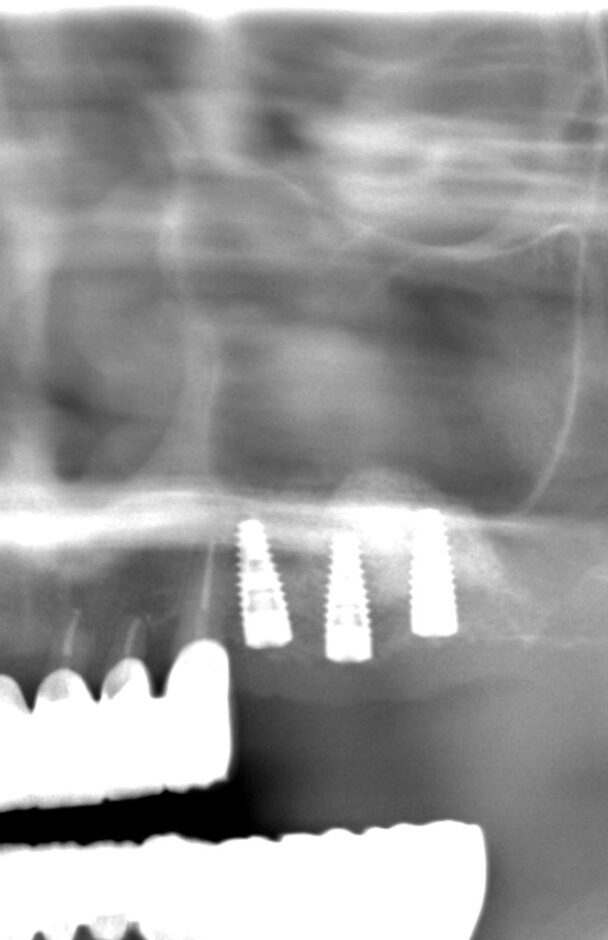

処置前のレントゲンです。

上の奥歯に歯がないのが分かると思います。

通常のレントゲンだけだと正確な診断ができないためCTを撮影します。

実際の処置後です。

下の歯と本数を揃えるため、計画を再立案し3本のインプラントを埋入しました。

インプラントの上にドーム状に広がっているのがサイナスリフトを行い填入された人工骨です。

予定通りの場所に、予定通りの方法でインプラント手術を終えることができました。